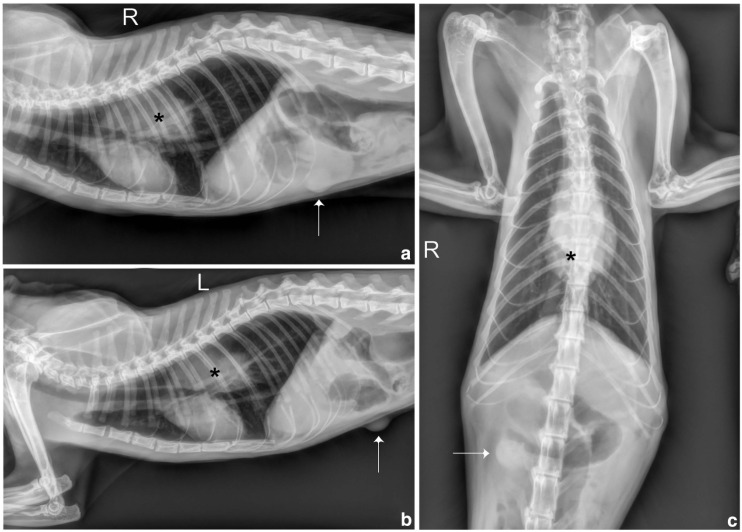

Case summary: An 11-year-old castrated male domestic shorthair cat presented with chronic regurgitation and weight loss. Despite a 2-month history of weight loss, regurgitation intensified over 4 weeks, occurring with every food intake, even on a semi-liquid diet. Physical examination revealed thinness and dehydration, and a focal oval mass was noted in the middle mediastinum on thoracic radiography. Oesophagoscopy identified a 6 cm neoformation almost completely obstructing the oesophageal lumen. Biopsies were taken and histopathology, positivity to melanoma triple cocktail and PNL-2 by immunohistochemistry led to the diagnosis of melanocytic neoplasm. Palliative debulking with argon plasma coagulation (APC) was performed, significantly improving the cat's quality of life for 2 months. The cat survived for 107 days after diagnosis.

Relevance and novel information: This case report describes the first report of melanocytic neoplasia originating from the oesophageal mucosa in a cat. In cats, melanomas outside the eyes are exceedingly rare and oesophageal neoplasms are exceptionally rare in veterinary medicine, particularly melanomas. The diagnosis relied on positive immunohistochemistry markers aligning with previous research. Treatment with APC emerged as a novel, potentially palliative approach, successfully alleviating regurgitation for 3 months. This underscores APC's potential in feline oesophageal neoplasia palliative care, which deserves further investigation in a broader feline cohort to confirm its efficacy. Overall, this report provides valuable insights into the diagnosis and treatment of oesophageal melanoma in cats.